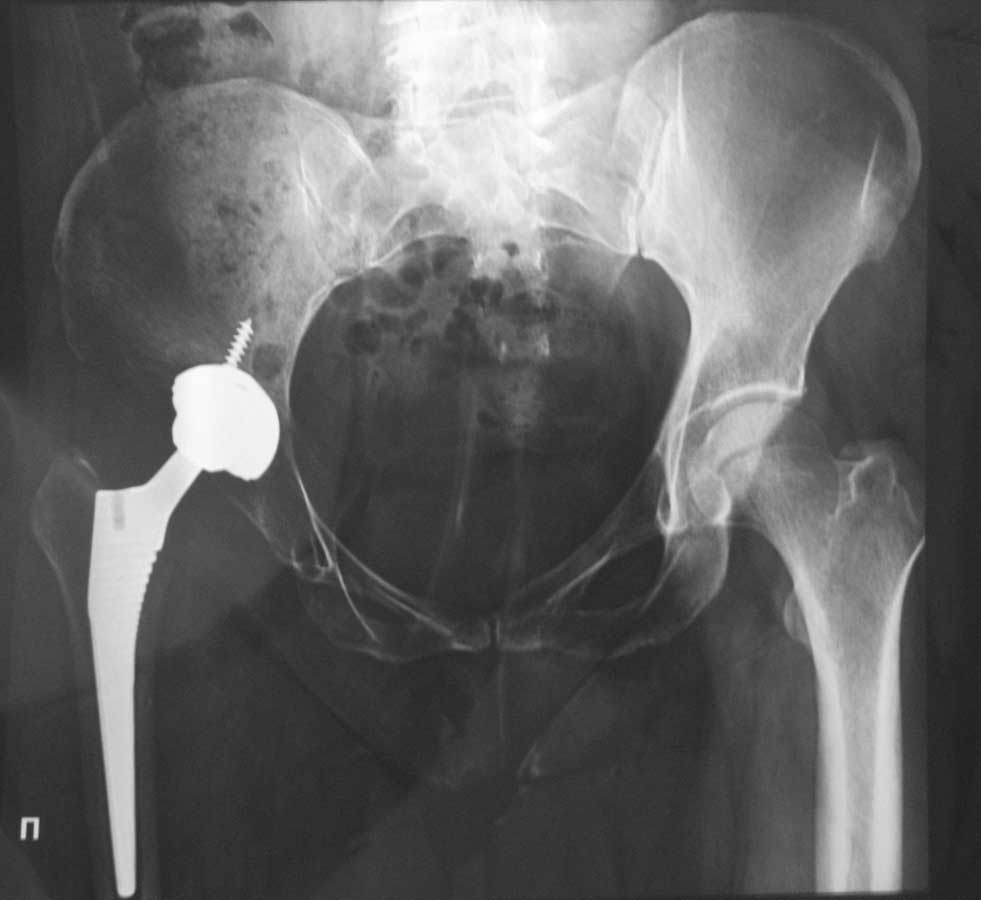

Здравствуйте, уважаемые коллеги! 7 января 2012 года нами была оперирована женщина 42 лет. Был установлен эндопротез керамика по керамике в ТБС.

Послеоперационный период спокойный. По истечению трех месяцев стала ходить без костылей. Но появилось боли в коленном суставе и произошла установка коленного сустава в вальгус. На рентгенах и КТ все пределах нормы. Что может быть, как больному помочь?Спасибо заранее.